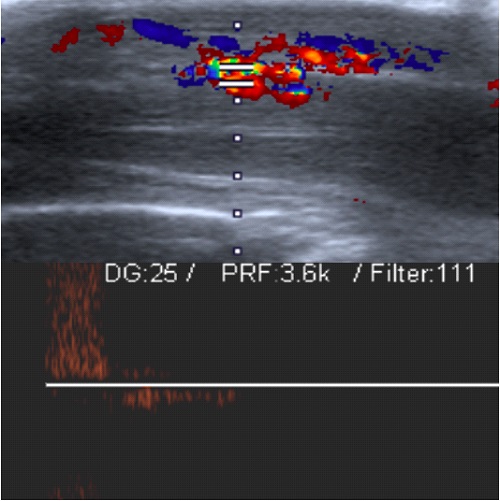

Ante dichos episodios se solicita hemograma y electroforesis de hemoglobinas con resultado normal (Hb A 95,5% (valor normal 96,8-97,8%), Hb A2 2,2% (valor normal 2-3,5%) y Hb fetal 2,3% (valor normal <6%). Glucosa-6-P-deshidrogenasa: 305 mU/10^9 (valor normal: 221-570). Tras descartar patología hematológica, se realiza una resonancia magnética de la columna dorsolumbar y sacra en la que no se observan hallazgos patológicos, y una ecografía Doppler peneana donde se observa una fístula arteriovenosa en el tercio medio de pene (Figura 1). Se realiza gasometría de los cuerpos cavernosos, que es compatible con sangre arterial (pH 7,305, pCO2 45,8 mmHg, pO2 168,7 mmHg), por lo que se diagnostica de priapismo de alto flujo secundario a fístula arteriovenosa congénita.

| Figura 1. Ecografía Doppler del pene en erección, que muestra flujo arterial y venoso, compatible con fístula arteriovenosa |

Distinguir entre priapismo de alto flujo, de bajo flujo y la erección prolongada recurrente es esencial para adecuar el manejo. Para el diagnóstico suele ser suficiente con una adecuada anamnesis y exploración física. El hemograma es la primera prueba complementaria a realizar con el objetivo de descartar procesos hematológicos. En caso de resultar normal, la prueba de elección es la ecografía Doppler peneana que permita descartar malformaciones vasculares a dicho nivel2.

La ecografía Doppler del pene es la prueba complementaria principal para el diagnóstico, pues permite visualizar la fístula vascular2. La punción-aspiración de los senos cavernosos no es necesaria, excepto si existen dudas diagnósticas, en cuyo caso se observará una gasometría con sangre oxigenada1,2. El abordaje del priapismo de alto flujo debe ser, en primera instancia, conservador, ya que hasta el 62% de los casos se resuelven de manera espontánea. Se recomienda un manejo conservador durante seis semanas con revisiones periódicas y ecografía Doppler cada dos semanas2. En caso de ausencia de resolución, se realizará arteriografía diagnóstica y terapéutica, que permite la embolización selectiva de la fístula1-3.